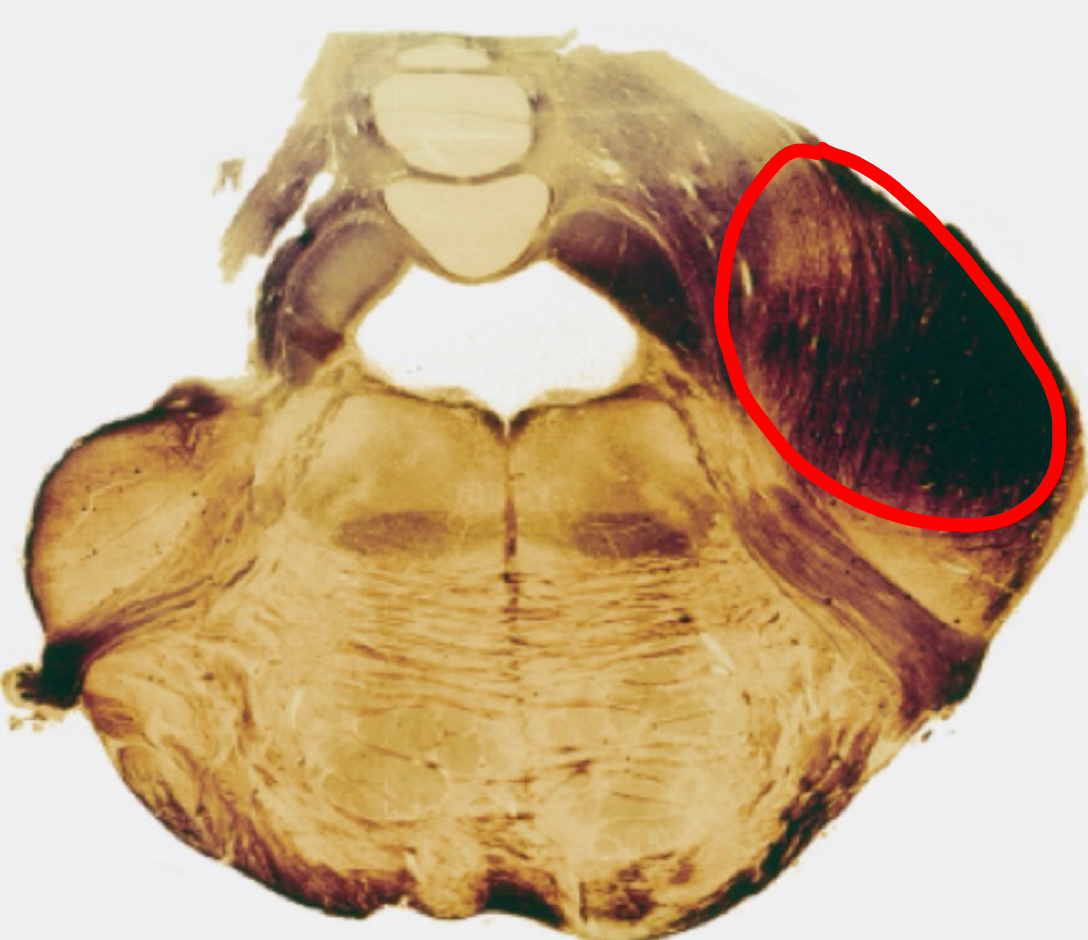

fastigial nucleus

interposed nucleus (globose + emboliform)

dentate nucleus

posterior lobe

vermis

tonsils

flocculus

nodule

cerebellar peduncles

4th ventricle